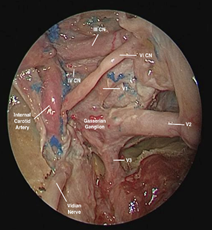

Transnasal endoscopic surgery was performed to attempt biopsy of the cranial nerves with suspected involvement. Complete resection of the lesion was ruled out due to involvement of the cavernous sinus and because there was no histopathological diagnostic confirmation. Initially, a maxillary antrostomy was performed, followed by a post-lacrimal maxillectomy for expanded access to the floor and medial wall of the nasal cavity. The posterior wall of the maxillary sinus was then removed to expose the pterygopalatine fossa. An incisional biopsy was performed in the neurovascular structures covering the palatine bone, with the infraorbital nerve as the lateral limit. Then, the sphenoid sinus was opened and dissected down to the floor, exposing the vidian nerve (Figures 3A and 3B). On the lateral wall, the foramen rotundum was opened to expose CN V2 (Figures 3C and 3D). All specimens were sent for frozen sections, which revealed carcinomatous infiltration of nerve fibers, conclusively demonstrating perineural tumor spread. Postoperative treatment consisted of radiation therapy alone.

Figure 3 Transnasal exposure (zero-degree endoscope) of pterygopalatine fossa and sphenoid sinus on the right. A: Identification of the foramen rotundum and pterygoid foramen after partial resection of the structures of the pterygopalatine fossa; B: vidian nerve resection; C and D: opening of the foramen rotundum and exposure and undermining of the maxillary nerve up to the cavernous sinus.

The main findings that suggest perineural spread are thickening and contrast enhancement of the nerves, as well as of the foramina or canals through which the affected nerves pass, with consequent obliteration of fat planes. Secondary findings such as muscle atrophy due to denervation are also red flags.3 Focal or linear contrast uptake along CN V2, the foramen ovale, or trigeminal cave should raise suspicion of perineural spread. The cranial nerves most commonly affected by perineural spread are the trigeminal and facial nerves. The Meckel”s cave in the left side was dissected to expose anatomically the most common site of perineural spread (Figure 7). The risk of perineural spread increases with tumor location, male gender, tumor growth, recurrence after treatment, and poor histological differentiation.12–14 Clinically, it is a challenging diagnosis, because approximately 40% of patients with perineural spread are asymptomatic. When present, the most common signs and symptoms are pain, paresthesia, and motor weakness.3

Figure 7 Transnasal dissection (zero-degree endoscope) of the Meckle’s cave in the left side. Trigeminal nerve, route of the perineural spread in the skull base.